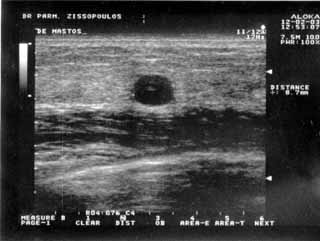

Oι τελευταίες 4 απεικονίσεις έγιναν με ειδικό για μαστό ηχοβολέα linear, εναλλασσομένης συχνότητος 7,5-10ΜΗΖ.